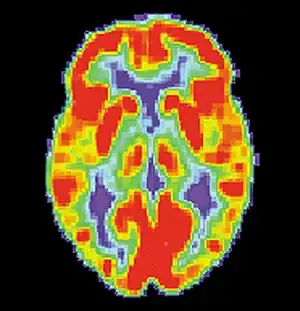

18F-fluorodeoxyglucose (18F-FDG) brain positron emission tomography (PET) may show a brain region of decreased glucose metabolism at a time between seizures; this hypometabolic region may correspond to the seizure focus, and PET scan is more sensitive for temporal lobe seizure focus localization compared to epilepsy arising from other brain lobes.[4] Single-photon emission computed tomography (SPECT) may show a region of decreased blood flow occurring 40-60 seconds after injection during the seizure; this reduced blood flow region may correspond to the seizure focus.[4]